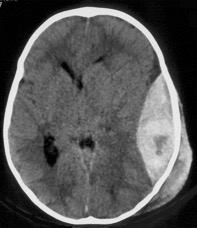

- parfois l’hématome est visible par transparence à travers l’os mince de l’enfant (Cf. ci-contre)

- elle commence par un ou plusieurs trous de trépan, qui permettent de confirmer la position de l’hématome

- on peut commencer à décomprimer l’HED par aspiration par le premier trou de trépan